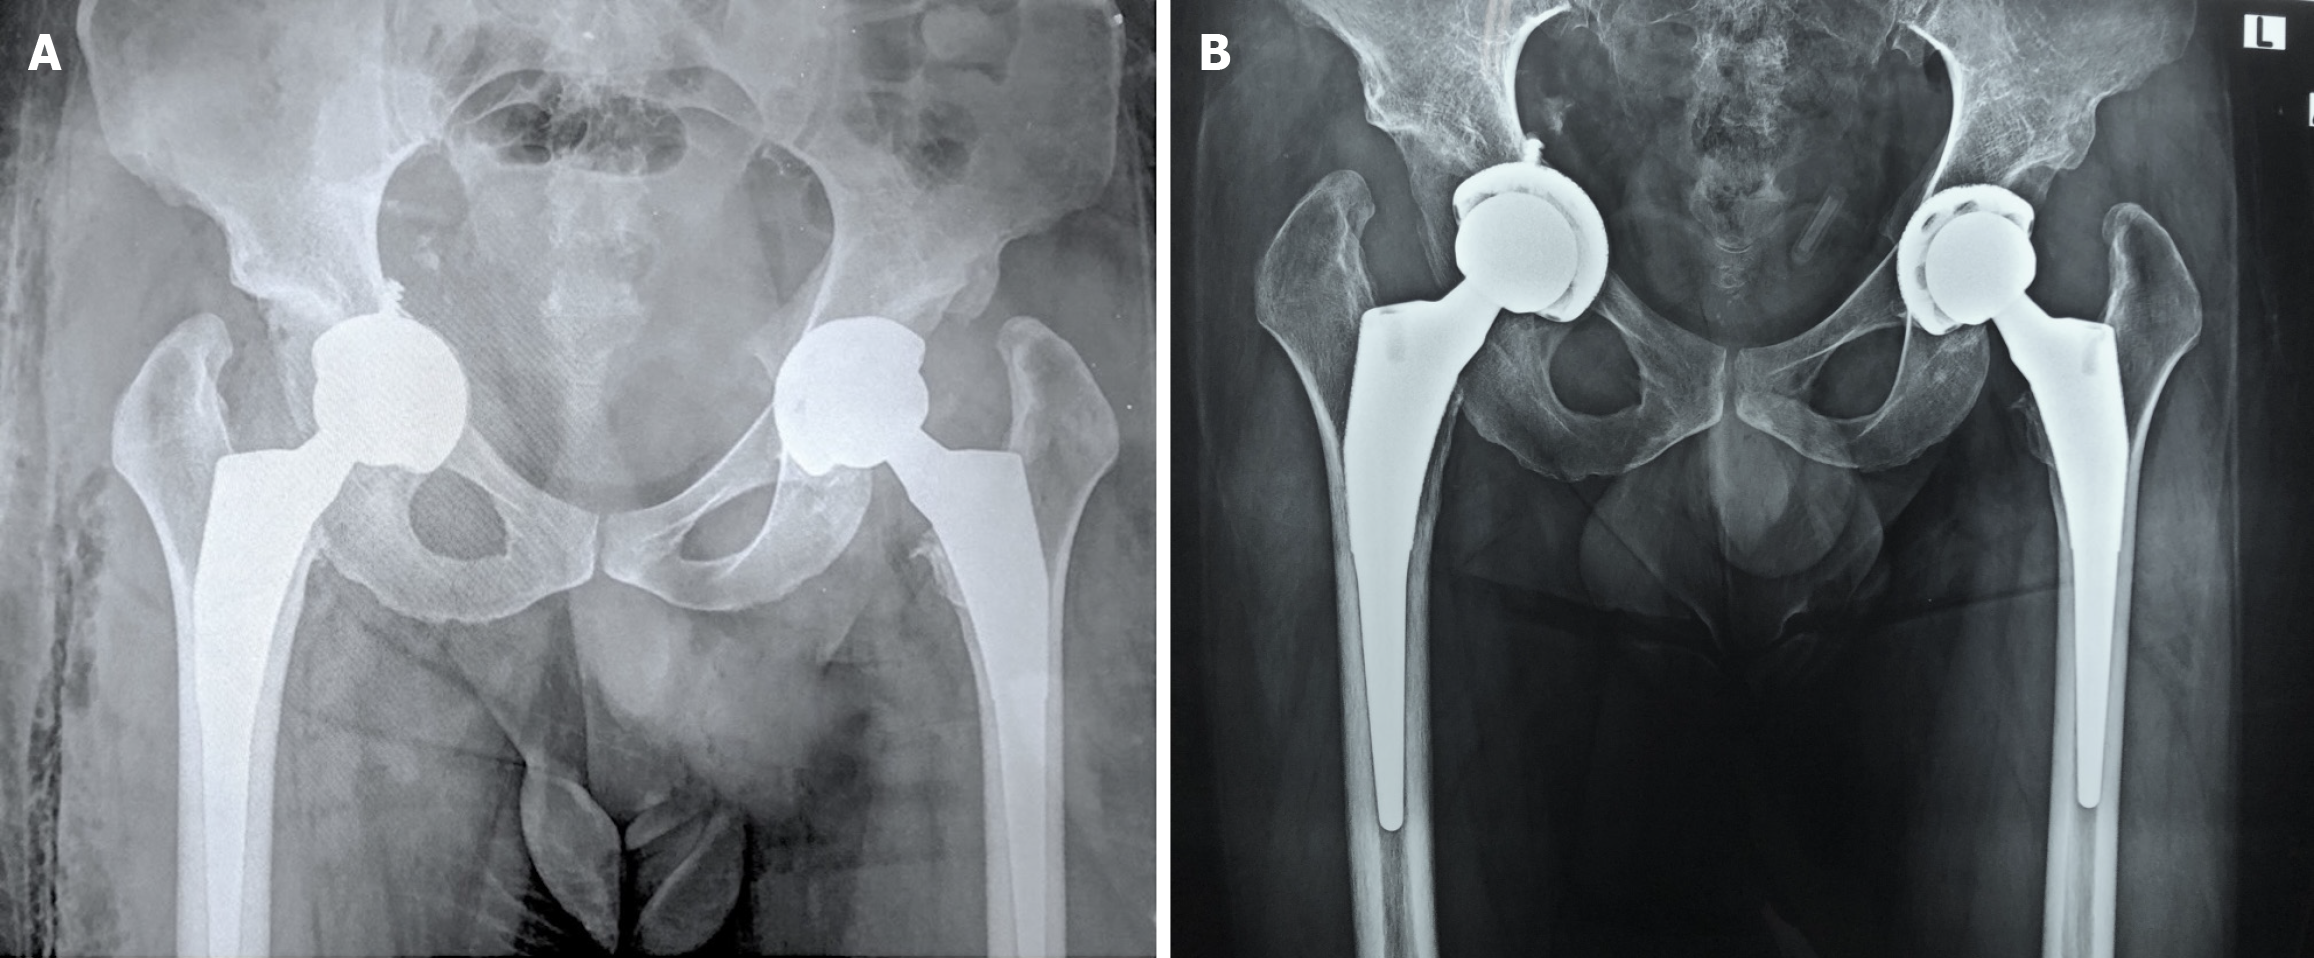

Figure 1 Serial pelvic radiographs.

A: Anteroposterior pelvic radiograph showing bilateral developmental dysplasia of the hip; B: Postoperative anteroposterior pelvic radiograph after left total hip arthroplasty (THA); C: Immediate postoperative anteroposterior pelvic radiograph after the right THA illustrating mild acetabular penetration by the transacetabular screw; D: A new postoperative anteroposterior pelvic radiograph on the same day after the right THA showing protrusion of the transacetabular screw into the greater sciatic notch.